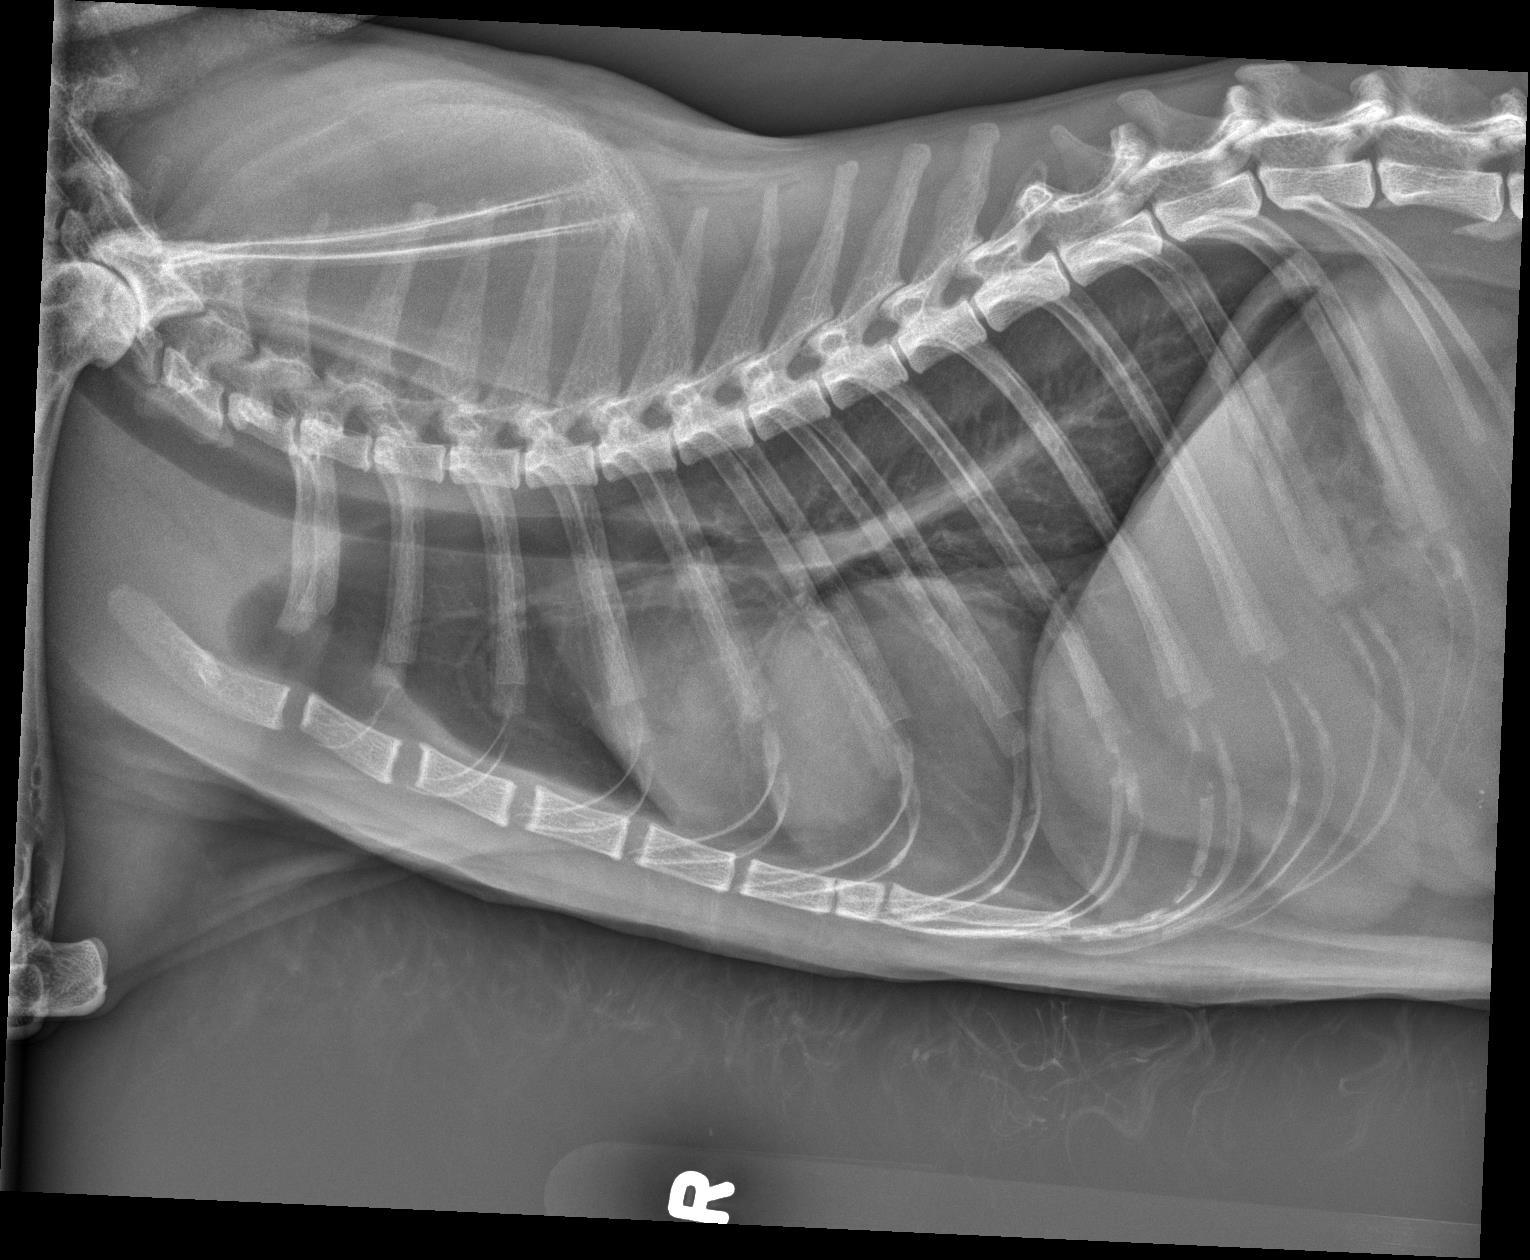

Orthogonal radiographs of the thorax are available for interpretation.

Within the caudal ventral thorax, directly adjacent to the diaphragm, there is a large, round, smoothly marginated, fat opaque structure that is causing dorsal and leftward deviation of the cardiac silhouette. The margins of the cardiac silhouette are distinctly identified superimposed with this structure on the lateral views.

The cardiac silhouette is normal in size. The pulmonary vessels, pulmonary parenchyma, and pleural space are normal.

The rounded structure in the caudal ventral thorax is suspected to represent fat opaque material and may be due to herniation/eventration of falcifom fat.

On the annotated image the cardiac margin remains visible when superimposed with the caudal structure. This indicates that those two are not of the same opacity. Furthermore the caudal structure is slightly more radiolucent compared to the cardiac outline.